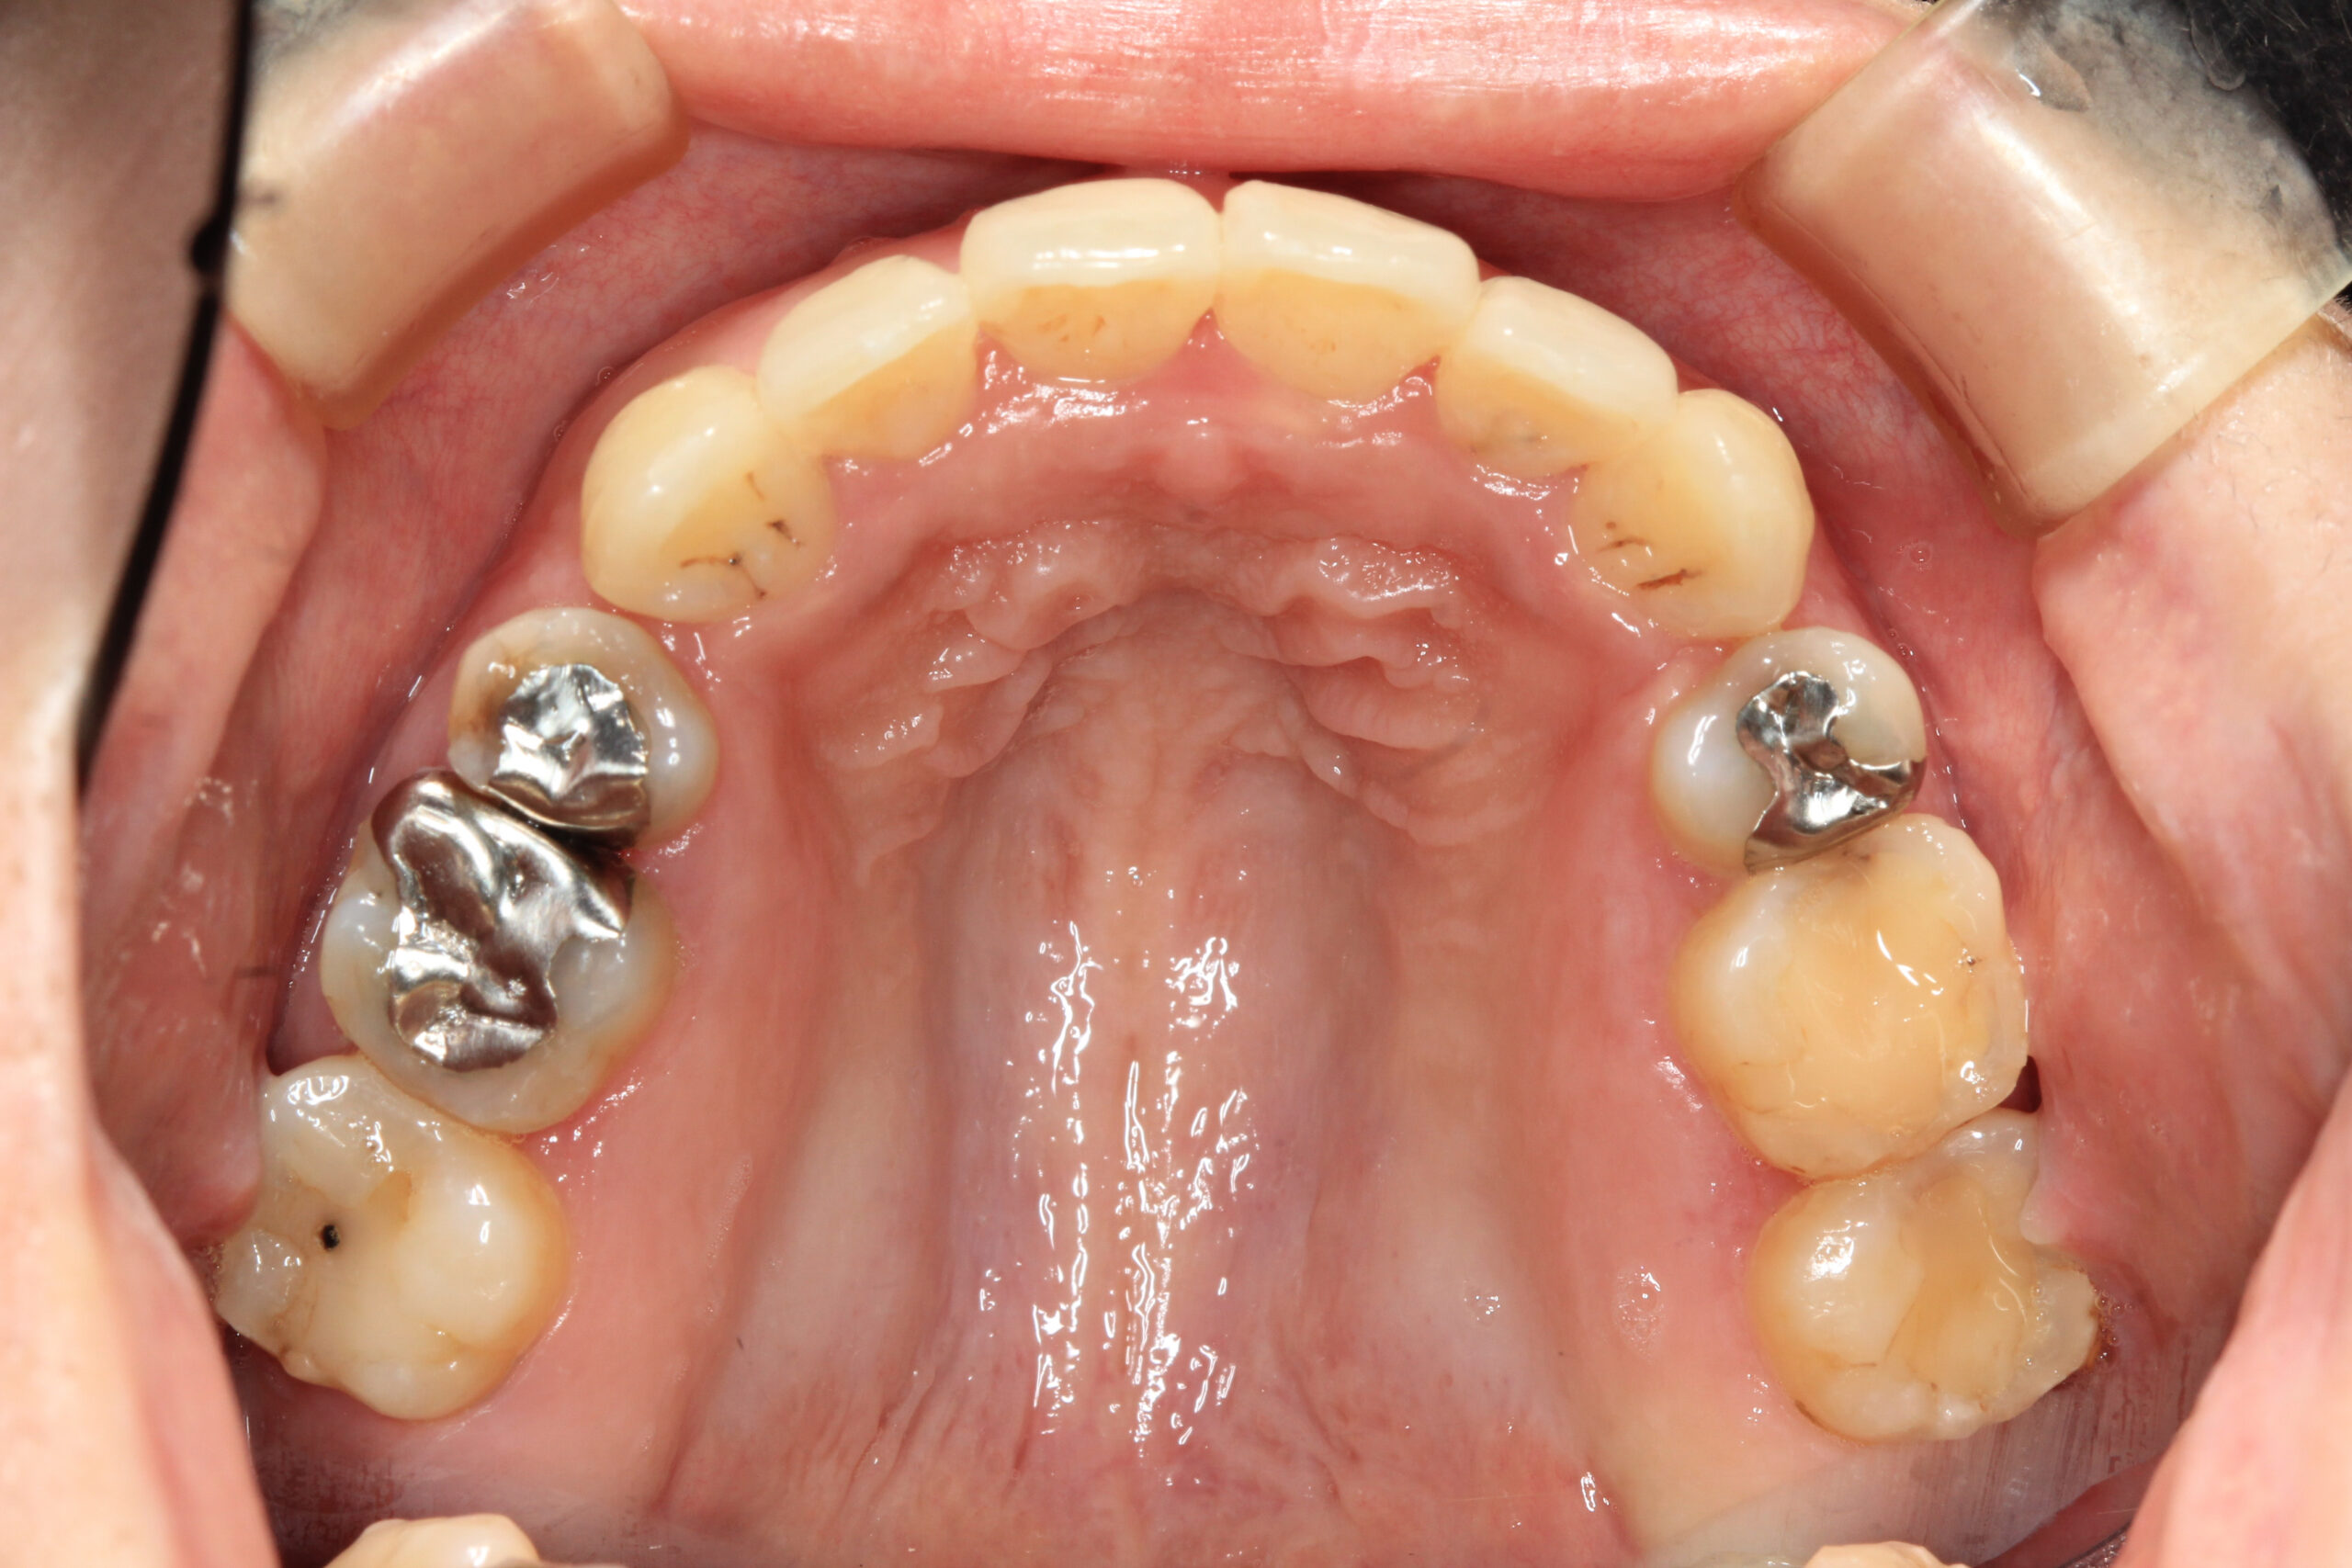

アーチが狭く前歯が出た状態です。

下顎もアーチが狭い為前歯にしわ寄せがきて翼状捻転していますね~